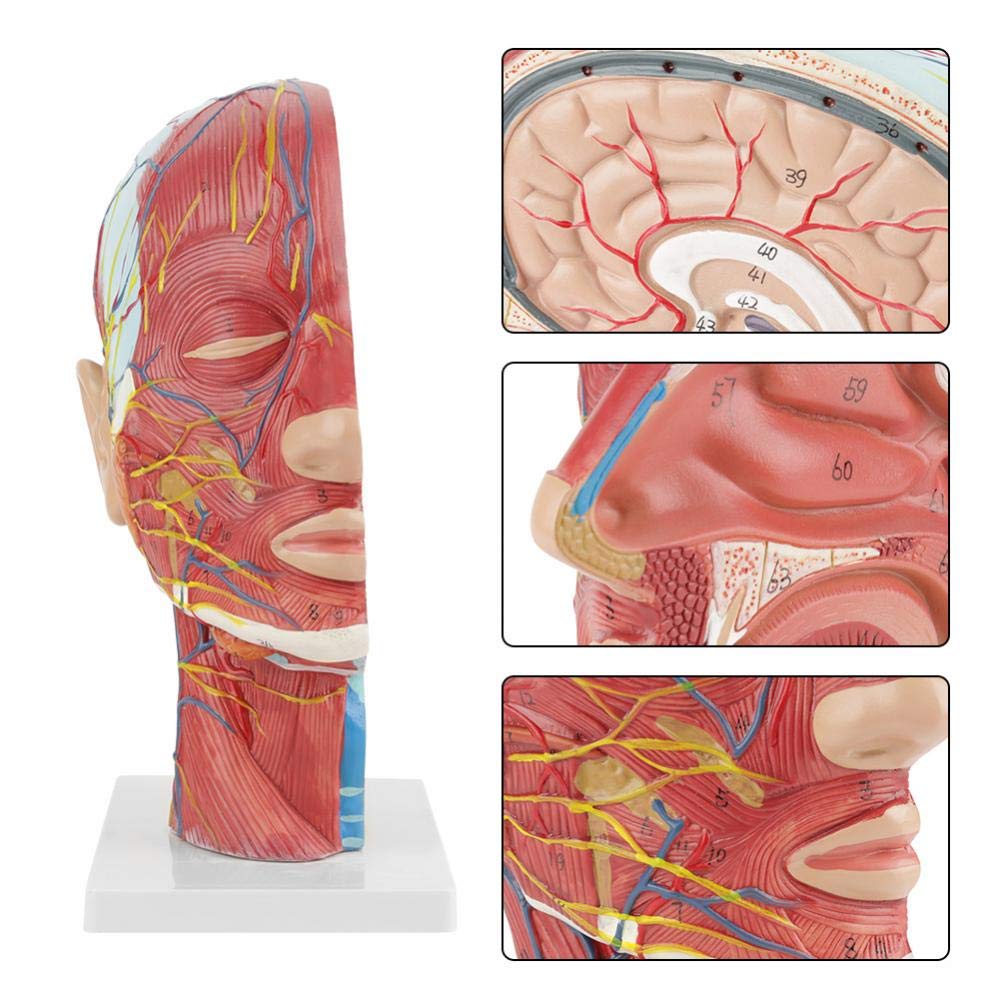

| Karatteristiċi | Il-mudell juri l-morfoloġija lokali tal-ġnub ta 'ġewwa u ta' barra tas-sezzjoni sagittali medjana tar-ras u tal-għonq, kif ukoll l-istrutturi tal-bastimenti tad-demm u n-nervituri, u hemm 84 partijiet li jindikaw sinjali b'kollox. |

【1: 1 Lifesize】 Sezzjoni medjana ta '1: 1 Natural Head & Neck Mudell tal-muskolu vaskulari newrali superfiċjali (naħa tal-lemin). Xogħol sabiħ. Toffri firxa sħiħa ta 'karatteristiċi anatomiċi.

【Mudell ta 'anatomija tal-moħħ ta' kwalità għolja, magħmul minn materjal tal-PVC mhux tossiku għall-ambjent, faċli biex jitnaddaf. Mudelli tal-anatomija huma miżbugħa bl-idejn u mmuntati bl-akbar attenzjoni għad-dettall.

【Mudell tal-muskolu newrovaskulari superfiċjali】 Dettaljat ħafna, numri mmarkati, li jistgħu jinqalgħu, japprofondixxu l-fehim tal-muskoli superfiċjali, bastimenti, nervituri u l-istrutturi interni tar-ras u l-għonq. Arterja ħamra, vetta blu, isfar-nerve.

【Karatteristiċi】 Juri l-muskoli superfiċjali tal-wiċċ espost; il-bastimenti tad-demm superfiċjali u n-nervituri tal-wiċċ u l-qorriegħa; l-istrutturi ta 'ġewwa tal-glandola parotida u l-passaġġ respiratorju ta' fuq; L-istruttura tas-sezzjoni trasversali sagittali tas-sinsla ċervikali.

Dan il-mudell juri dettalji tal-għonq tar-ras tal-lemin u s-sezzjoni sagittali tan-nofs tal-bniedem. inkluż is-superfiċjali

muskoli tal-wiċċ espost; il-bastimenti tad-demm superfiċjali u n-nervituri tal-wiċċ u l-qorriegħa; l-istrutturi ta 'ġewwa

tal-glandola parotida u l-passaġġ respiratorju ta 'fuq; L-istruttura tas-sezzjoni trasversali sagittali tas-sinsla ċervikali.

Il-mudell wera l-morfoloġija lokali tas-sezzjonijiet sagittali medjali u laterali tar-ras u l-għonq u l-istrutturi vaskulari u tan-nervituri tiegħu, b'total ta '100 indikatur tas-sit.

Dan il-mudell huwa mudell ta 'muskolu newrovaskulari superfiċjali ta' ras u għonq naturali, komponent 1, li juri d-dettalji tar-ras tal-lemin u l-għonq u s-sezzjoni sagittali medjana, inklużi l-muskoli superfiċjali esposti tal-wiċċ, bastimenti superfiċjali tal-wiċċ u l-qorriegħa, in-nervituri u l-istruttura medjali tal-glandola parotida u l-passaġġ respiratorju ta 'fuq, u l-istruttura tas-sezzjoni sagittali tas-sinsla ċervikali